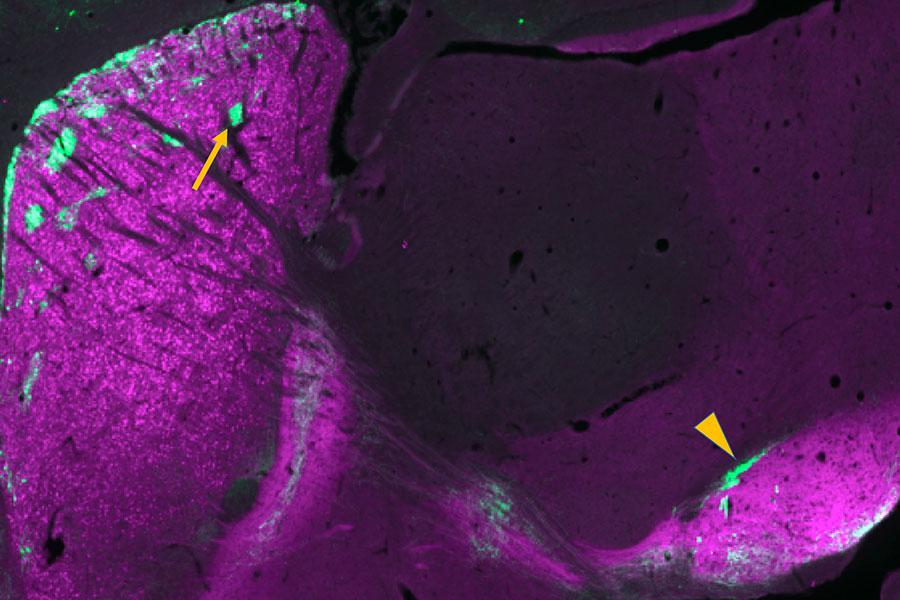

A new brain imaging study explored how different levels of the brain’s excitatory and inhibitory neurotransmitters are linked to math abilities.